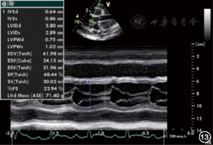

| M型超声(心室波群) | |||||

| 左心室 | 常用于测量左心室内径和射血分数,正常值和常见异常同二维超声(图13) | 左心室流出道梗阻时SAM征(图14) | 舒张末期测量内膜至内膜的垂直距离,取样线置于二尖瓣瓣尖水平并垂直于室壁,当心尖上翘取样线不能垂直于室壁时,不能采用此方法 | ||